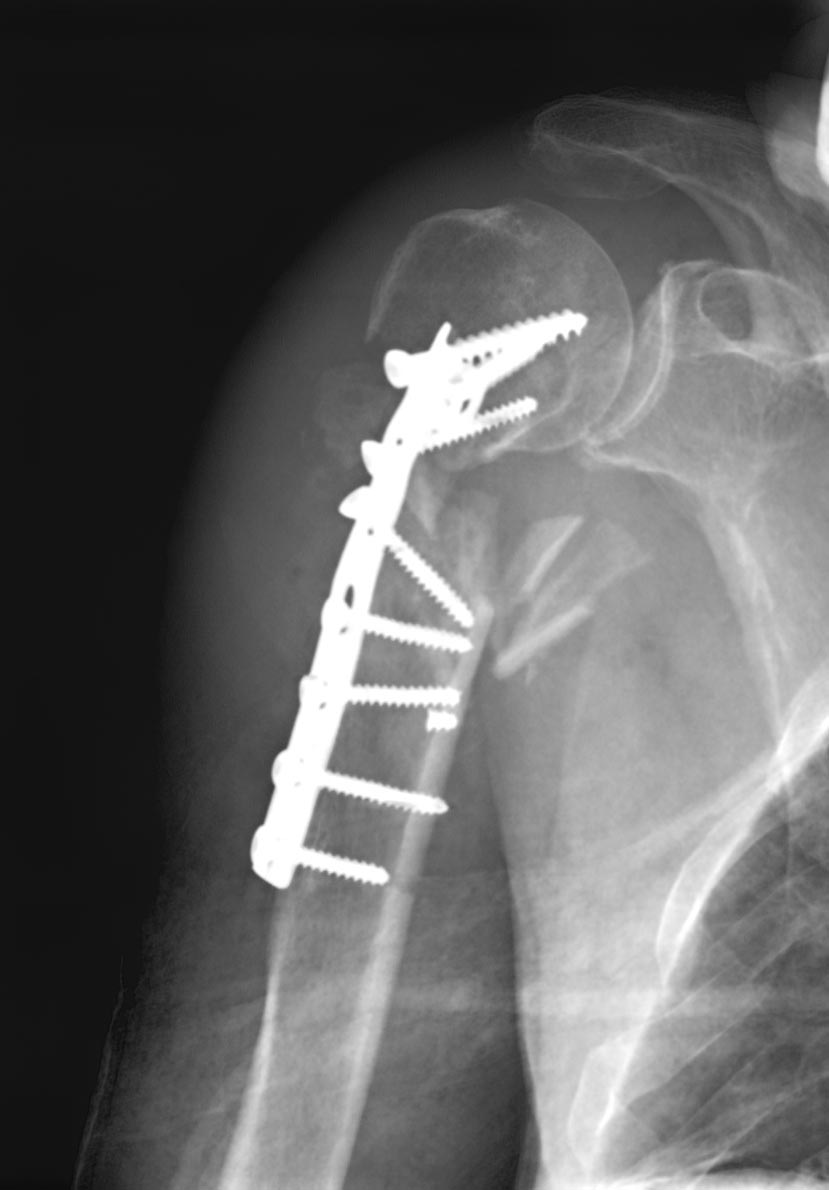

Перелом хирургической шейки плеча, 1947 г.р. Переведен из районной

больницы, оперирован 3 дня назад Т-образной пластиной.

Что с этим делать сейчас? Со слов, оперирующего хирурга

жуткий остеопороз (головка как скорлупа).